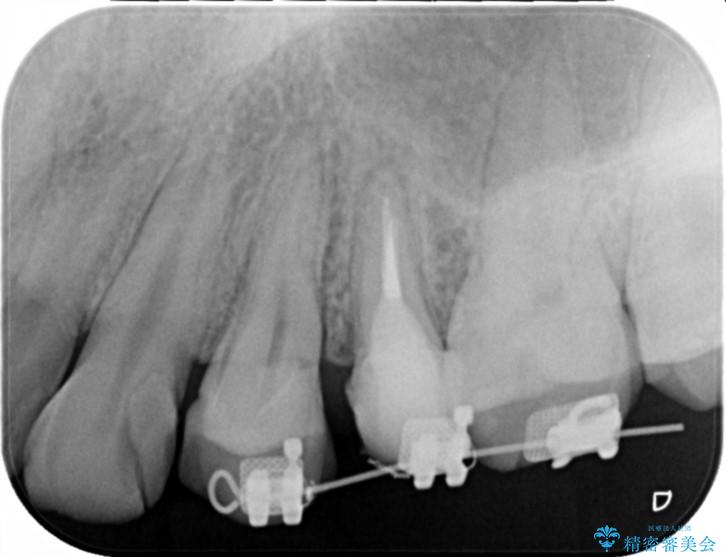

- 歯ぐきの腫れや、歯の内部が黒く見えることからの虫歯の治療を求めて来院されました。

虫歯が大きかったことから、神経の温存はできたものの歯ぐきよりも深い虫歯の問題を解決するため部分矯正治療を併用したセラミック治療を行うこととしました。

当初、歯ぐきよりも深い虫歯のぞんざいや、歯のポジションに問題がありましたがマルチブラケットを用いた部分矯正を行うことで適切な位置へと歯を移動させ、歯周環境を整えたセラミック治療を行うことができました。